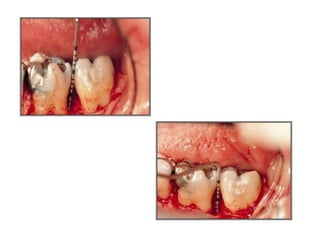

A sulcular incision full thickness flap is reflected. A three wall

intrabony defect is visualized at the distal of the first molar.

Placement of demineralized freeze-dried bone allograft is

accomplished with light incremental pressure so that the graft

overfills the defect. The root surface has been treated with citric

acid (pH 1) and the defect has been decorticated.

A monofilament suture is used to close the flaps by primary

closure.